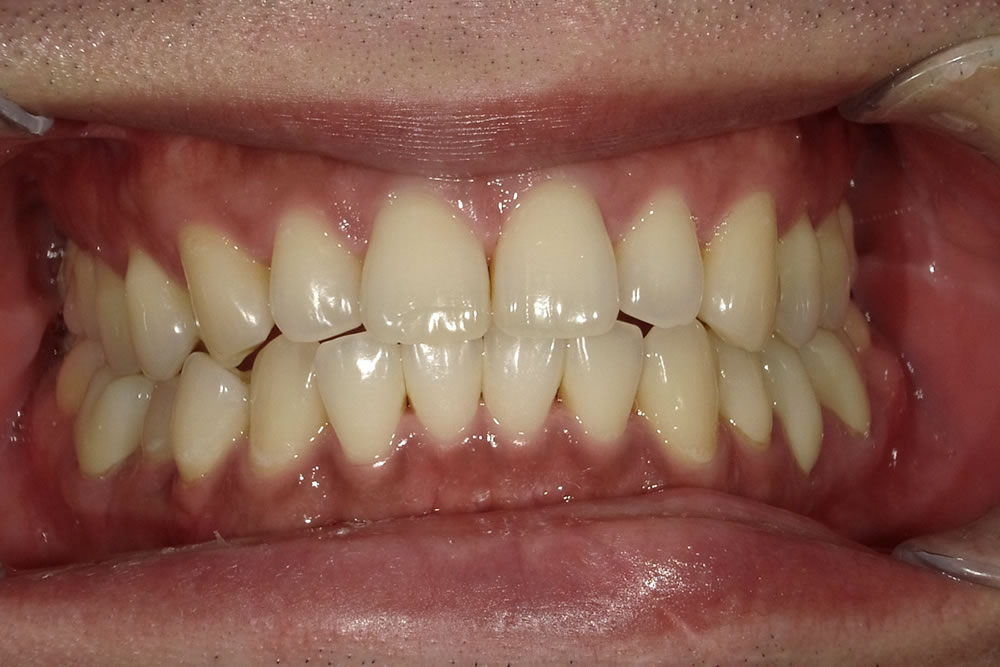

マウスピース矯正(インビザライン)で八重歯を改善した症例

年齢

30代

性別

女性

症例を見る